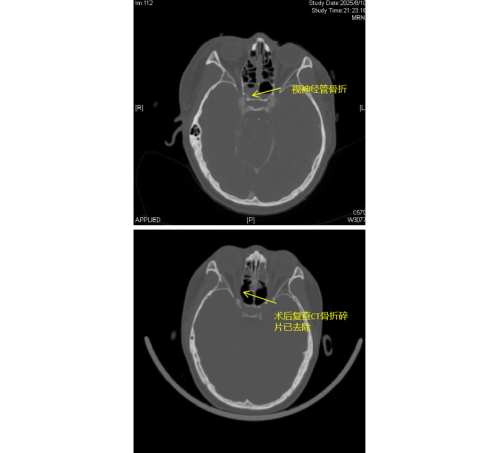

)急诊科。经检查发现,李琦存在颅底多处骨折、面颅多发骨折,尤其危急的是右侧视神经管骨折,碎裂的骨片直接压迫视神经及邻近的颈内动脉,导致右眼瞳孔散大、对光反射消失,视力完全丧失,病情极为危重。

由于视神经管周围解剖结构复杂,上方毗邻前颅底,下方紧邻颈内动脉和海绵窦,稍有不慎就可能导致脑脊液鼻漏、视神经断裂甚至颈内动脉破裂出血等严重后果,因此视神经的特殊位置被视为“手术雷区”。加之操作空间小,手术难度大,对于医生而言是一个巨大的挑战。视神经与鼻窦相邻,用鼻内镜经鼻窦进行视神经管减压手术,视野清楚、损伤最小。在手术过程中,康晓明医生利用高清鼻内镜,精准地清除了压迫视神经的骨折碎片,有效降低了神经压力。

手术完成后即刻观察到李琦右眼对光反射恢复灵敏,经过系统的治疗,其右眼视力已恢复至0.1,术后效果显著。目前,李琦正在进一步康复治疗中。此类高难度手术的成功,不仅展现了医院在多学科协作和急重症救治方面的综合实力,也为复杂颅底外伤患者带来了新的希望。